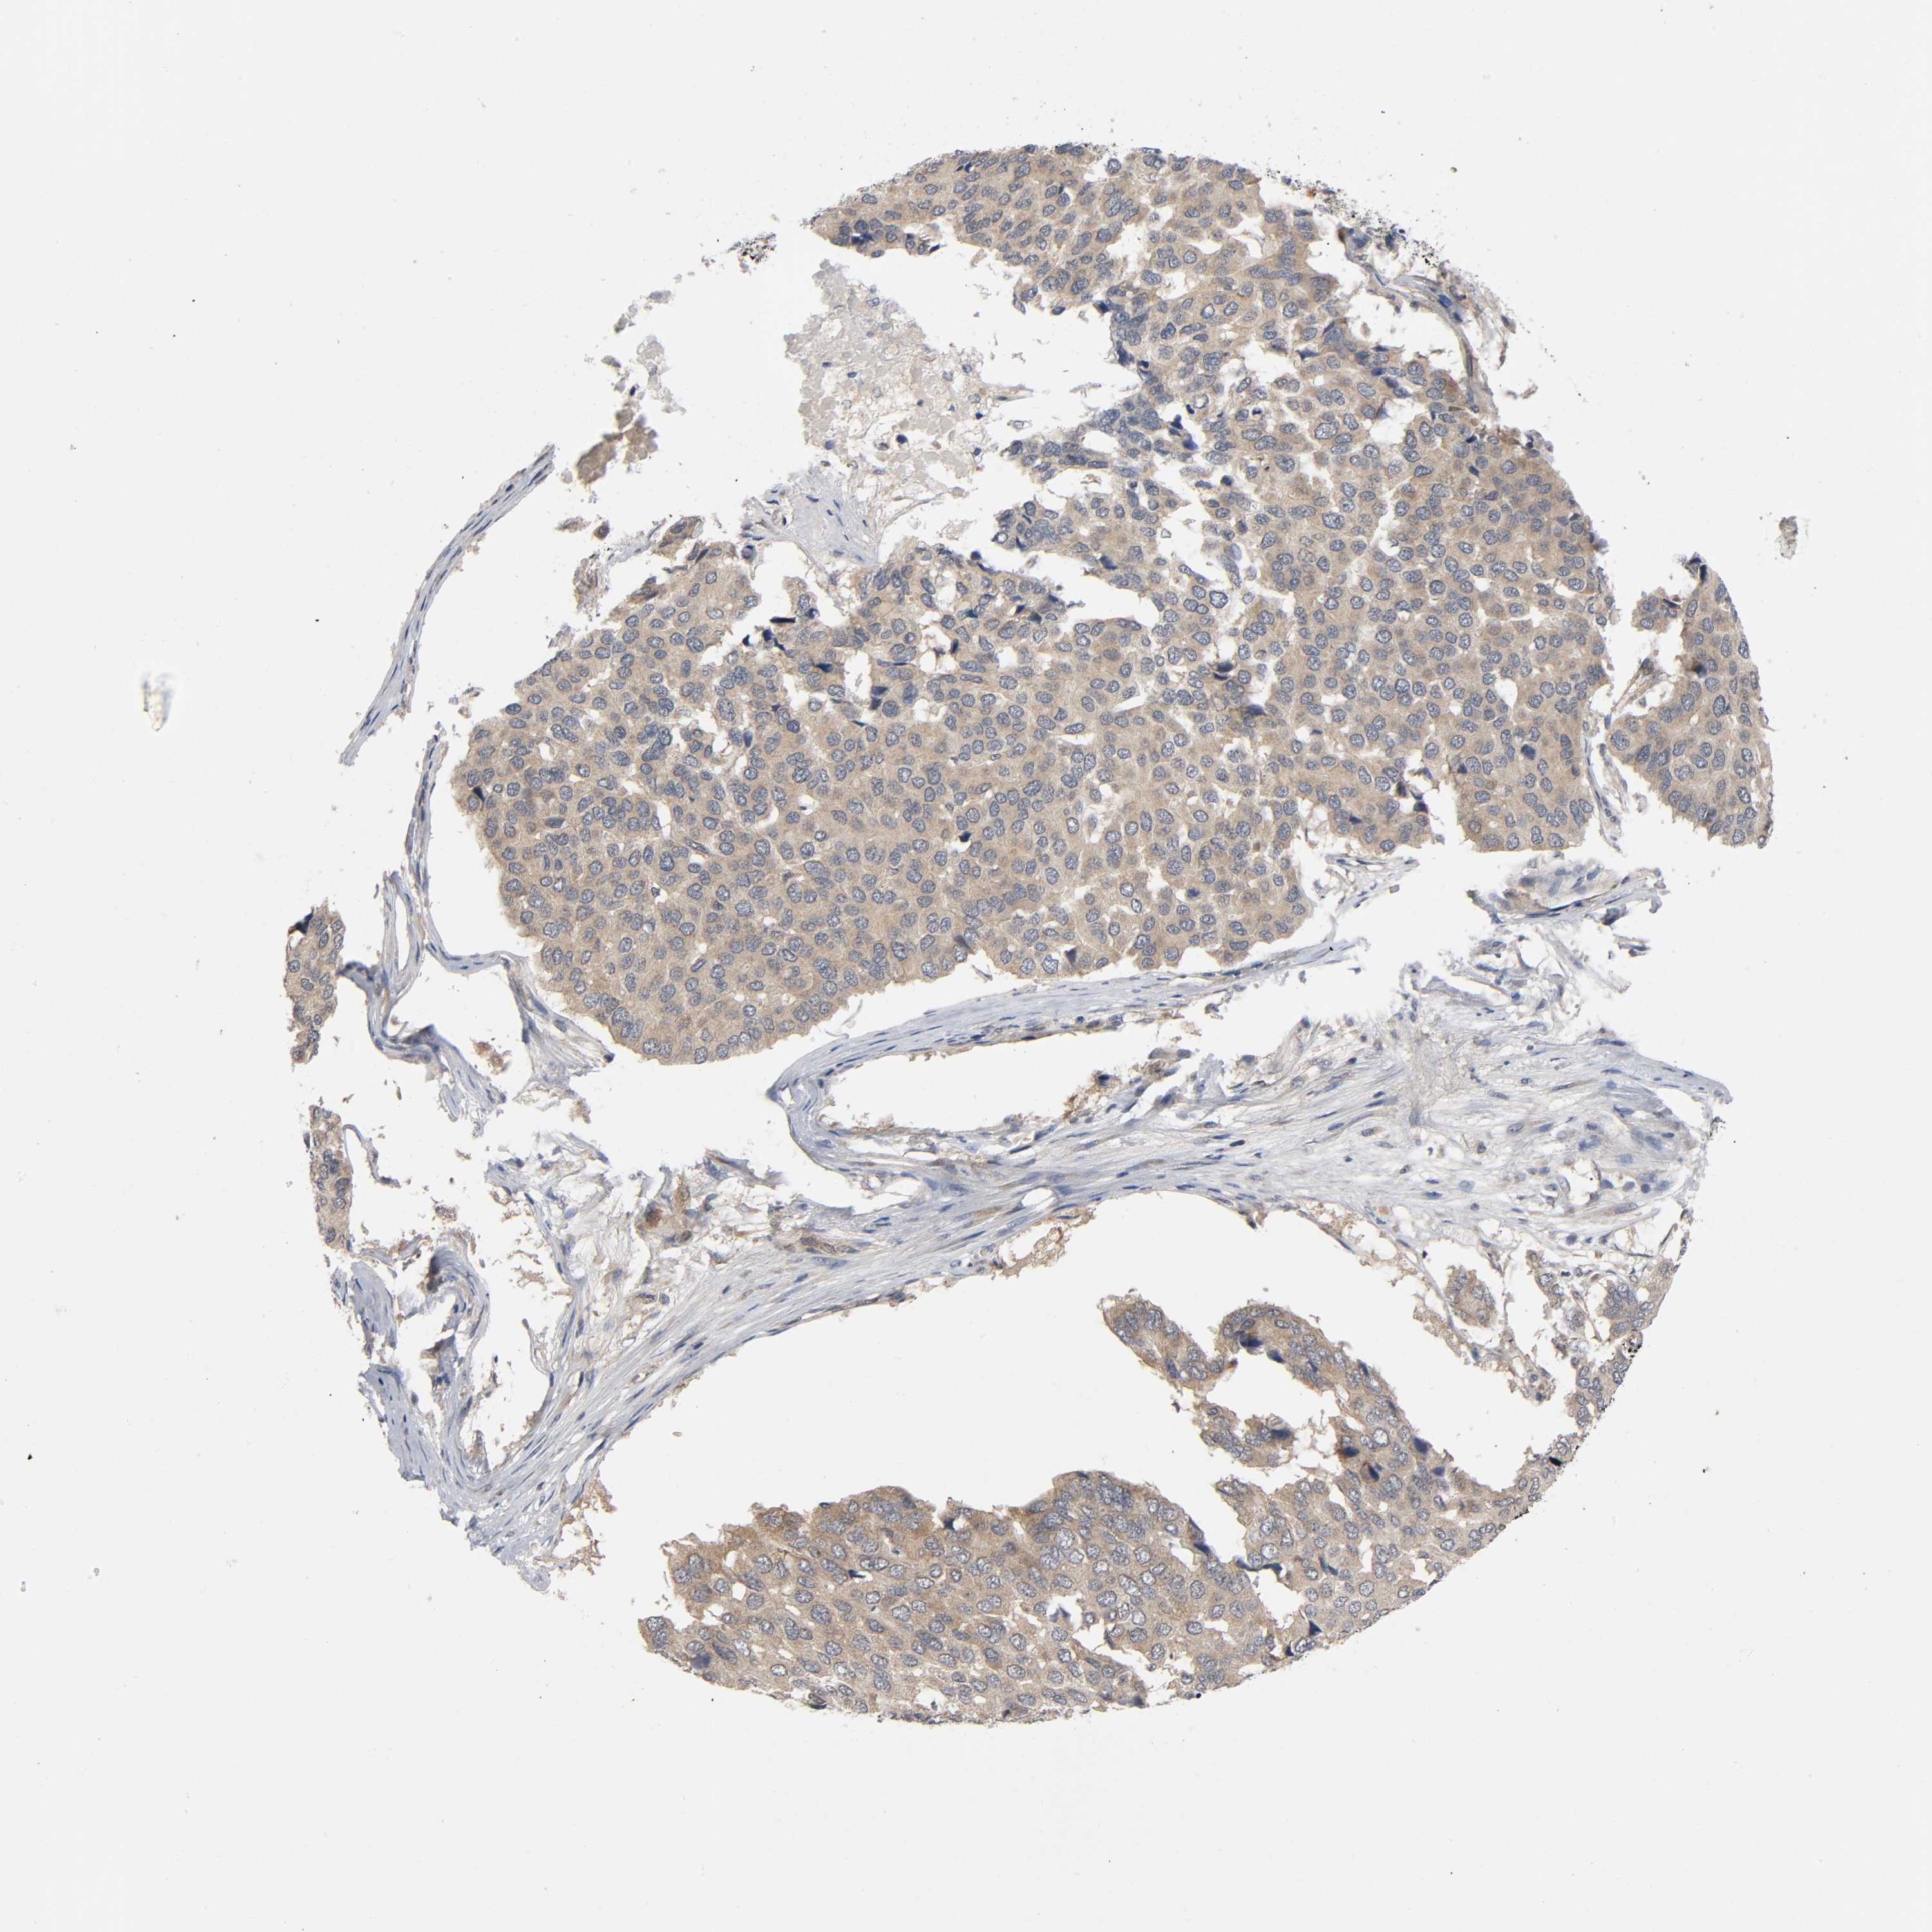

PANCREATIC CANCER - Protein expressioni

A mouse-over function shows sample information and annotation data. Click on an image to view it in a full screen mode. Samples can be filtered based on level of antibody staining by selecting one or several of the following categories: high, medium, low and not detected. The assay and annotation is described here.

Note that samples used for immunohistochemistry by the Human Protein Atlas do not correspond to samples in the TCGA dataset.

Antibody stainingi

Antibody staining in the annotated cell types in the current human tissue is reported as not detected, low, medium, or high, based on conventional immunohistochemistry profiling in selected tissues. This score is based on the combination of the staining intensity and fraction of stained cells.

Each image is clickable and will lead to virtual microscopy that enables deeper exploration of all samples and also displays staining intensity scores, fraction scores and subcellular localization as well as patient and tissue information for each sample.

Antibody CAB004463

Antibody CAB069396

Staining

High

Medium

Low

Not detected

Intensity

Strong

Moderate

Weak

Negative

Quantity

>75%

75%-25%

<25%

None

Location

Nuclear

Cytoplasmic/membranous

Cytoplasmic/membranous,nuclear

Adenocarcinoma, NOS

Adenocarcinoma, metastatic, NOS